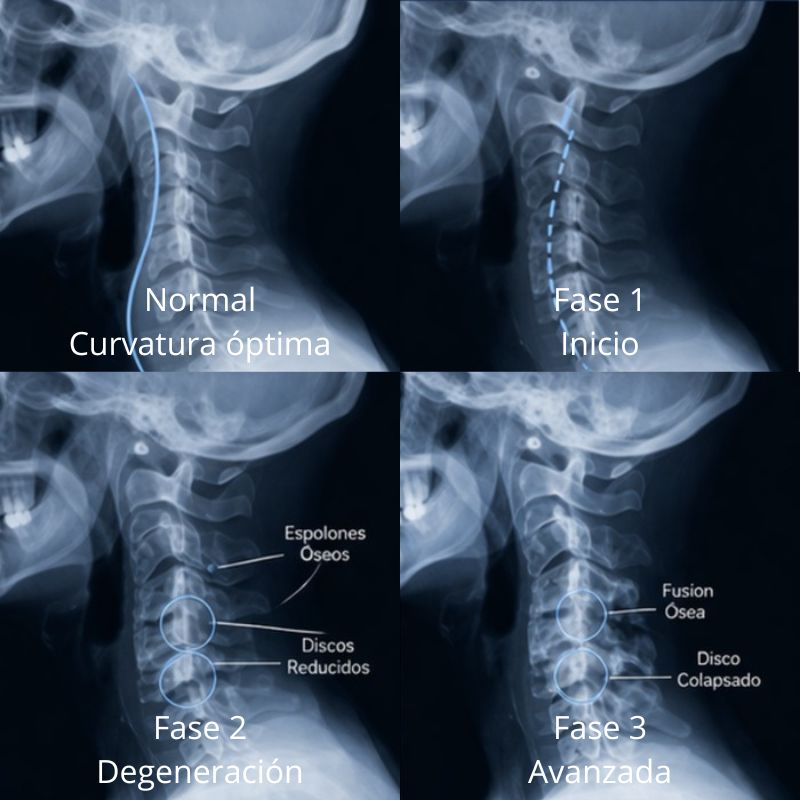

Cuatro fases en el proceso

La degeneración espinal es un proceso. Tanto si haces cuatro fotografías del proceso como si haces veintitrés; es un proceso. Utilizamos el modelo de cuatro fases basado en el libro «Managing Low Back Pain» (Cómo controlar el dolor de espalda), de W.H. Kirkaldly-Willis y Thomas Bernard, Jr., además del libro «Anatómico-Roentgenographic Studies of the Spine» (Los Estudios Anatómico-radiológicos de la columna vertebral), de Lee A. Hadley, M.D. Esto destaca de manera suficiente la diferencia entre cada fase y los miembros de nuestra consulta pueden apreciar lo que están viendo.

CURVATURA NORMAL

Aunque este proceso puede ocurrir en cualquier parte de la columna vertebral, es más fácil de ver en la columna cervical (cuello). Así es como la vista lateral del cuello debería verse. Desde el lado, el cuello debe tener una elegante curvatura hacia adelante. Los bordes de cada hueso están bien definidos. Debe haber el mismo espacio discal entre cada hueso y las aperturas de las raíces nerviosas deben ser claras y sin obstrucciones.

Esto sería considerado una curvatura «normal» del cuello visto lateralmente.

LA PRIMERA FASE

Debido a un estrés físico sobre la columna vertebral o el cuerpo, en esta primera fase podemos observar una pérdida de curvatura. Las 7 vértebras cervicales del cuello, deben tener una curvatura, porque es gracias a ella, que se mantiene la amortiguación del peso de la cabeza, sobre el resto de la columna. Veremos los cambios en las fases siguientes, resultando que de un aumento de peso encima de las vértebras, éstas, intentarán hacerse más fuertes.Dejada sin tratar esta fase irá progresando en la próxima.

LA SEGUNDA FASE

Si se descuida, en la segunda fase, las superficies articulares pierden sus bordes claramente definidos como los primeros signos de espolones óseos se hacen visibles en las vistas de rayos-X. Algunos creen que el cuerpo detecta la inflamación que acompaña, como la señal de un hueso roto. Se inicia el proceso de depósito de sales de calcio. Sin estar en un molde para evitar el movimiento, la fusión no se produce. Dejada sin tratar esta fase irá progresando en la próxima.

TERCERA FASE

Si todavía no se corrige, el problema se agrava en la Fase Tres. Sorprendentemente, el dolor y otros síntomas evidentes puede que aún no aparezcan. Pero, finalmente, el cuerpo con éxito «repara el hueso roto.» Este proceso puede durar años. Su presencia, pone en cuestión la afirmación que muchos miembros de la consulta hacen ,de que estaban «… bien hasta la semana pasada cuando me agaché para atarme los zapatos.» ¡Eso no es lo que los rayos X nos dicen! Dejada sin tratar esta fase irá progresando en la próxima.